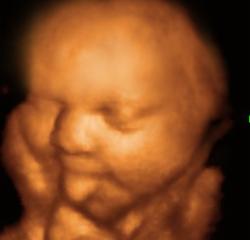

Фотоконкурс! "Самое прикольное фото с УЗИ"!

Добрый день дорогие девочки! Предлагаю вам не много отвлечься и поучаствовать в фотоконкурсе "Самое Прикольное фото с УЗИ"!!!

4. Принимаются любые фото с вашего УЗИ и 2D, и 3D, и 4D.